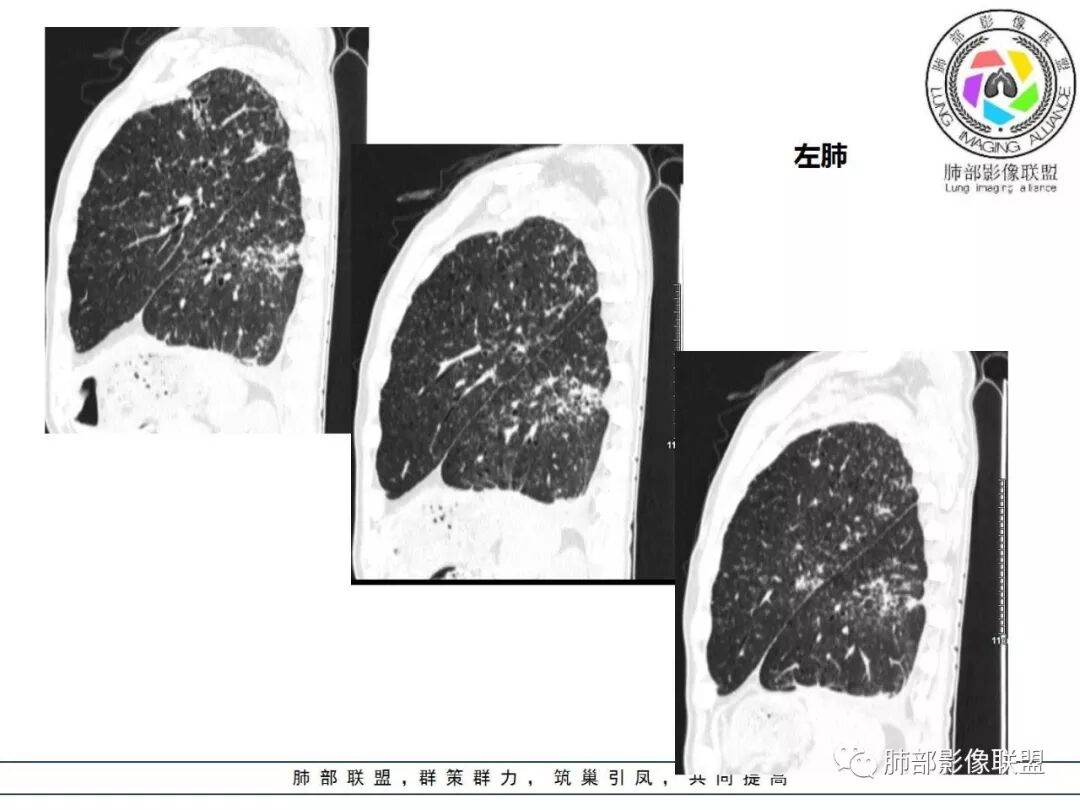

双肺间质性病变,中央间质增厚,胸膜下间质增厚,左侧胸膜肥厚,胸廓变小,肋间隙变窄。

对,大的支气管血管周围

胸部CT:两肺弥漫病灶,磨玻璃影,少许实变,部分累及胸膜,磨玻璃区可见囊?少许胸腔积液,两肺可见结节,支气管血管束增粗,小叶间隔增厚,支气管走形有扭曲扩张,可见纤维化。气肿、大泡。考虑:感染性病变,PCP?查下HIV,CD4,G等。鉴别结核、结缔组织病肺浸润。

胸部CT:两肺弥漫病灶,中央间质分布为主,部分位于胸膜及叶间裂旁,磨玻璃影,斑片影,部分实性结节,肺气囊,支气管血管束增粗,小叶间隔增厚,叶间裂不均匀增厚,支气管走形有扭曲扩张,可见纤维化、气肿、大泡。考虑:LIP加MALT。鉴别PLCH、PCP、结核、结缔组织病肺浸润。

双肺弥漫性病变,多发磨玻璃密度及小叶间隔增厚,大部分沿支气管血管束分布,伴支气管轻度扩张,以午后及晚上发热为主,考虑感染性病变,间质性结核可能大,另双肺多发肺气囊,LIP待排

病变一般沿血管支气管束分布或小叶分布,一般上肺多于下肺(这与常见继发性肺结核分布相若)。

常会伴有其他继发性肺结核病灶,如斑片影、结节影,树芽征,新旧不等改变。

2. 肺气肿背景(小叶中心性肺气肿);双肺多发病灶整体沿血管支气管束及胸膜下分布,以上叶及下叶背段分布为主,有实变及GGO,边界清楚,有树芽,小叶间隔及中央间质增厚,叶间裂见到多发结节,部分支气管不规则牵拉扩张,提示病灶纤维化明显,结合临床病史,考虑病灶为间质性感染,肺门及纵隔内有钙化淋巴结,小叶间隔结节,考虑淋巴道增值性疾病可能,综合常规要怀疑间质性肺结核。